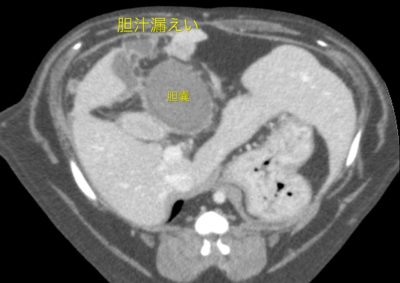

胆嚢破裂に対する胆嚢摘出術〜空腸栄養カテーテル設置